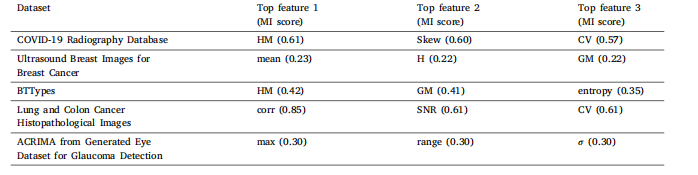

Table 6Top three selected features from 26 features set for each dataset based on MI after employing two-stage feature selection algorithm (ZFMIS).

表6 采用两阶段特征选择算法(ZFMIS)后,基于互信息(MI)从26个特征集中为每个数据集选出的前三名特征。